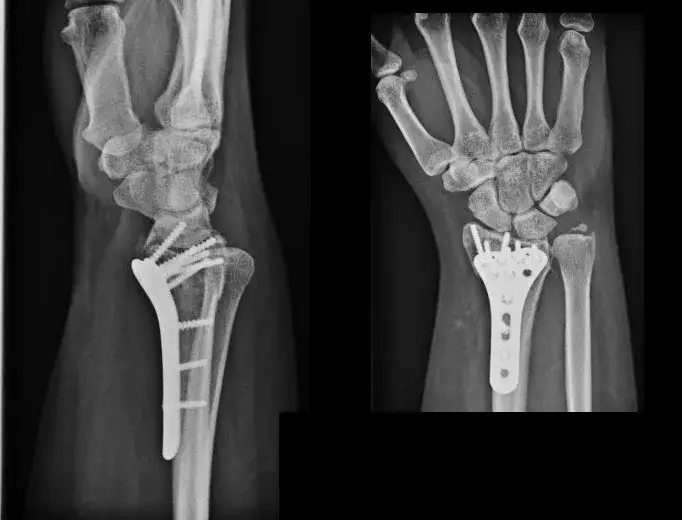

Leczenie operacyjne (dla III stopnia lub powikłanych urazów):

- W przypadku całkowitego zerwania więzadeł (III stopień), zwłaszcza u osób aktywnych fizycznie, może być konieczna operacja. Jej celem jest rekonstrukcja uszkodzonych więzadeł, aby przywrócić stabilność stawu.

- Po operacji również niezbędna jest intensywna rehabilitacja, która jest kluczowym elementem powrotu do pełnej sprawności. Bez niej nawet najlepiej przeprowadzona operacja nie przyniesie oczekiwanych rezultatów.